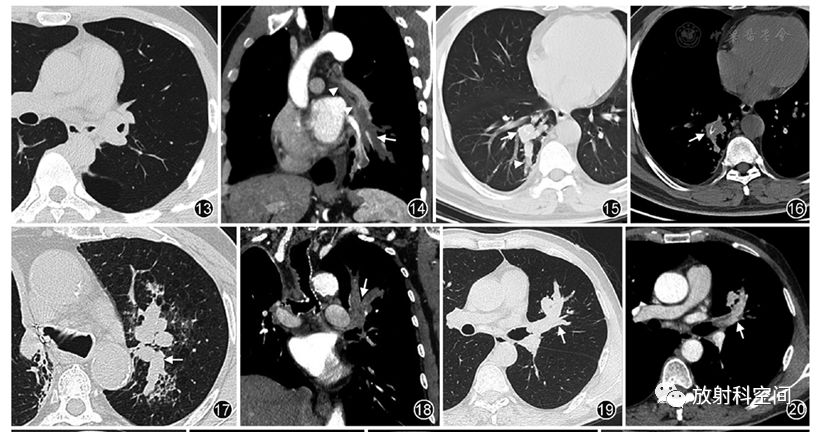

俊豪老师肺部粘液栓病变